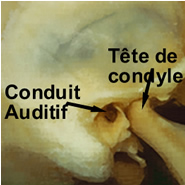

la Mâchoire